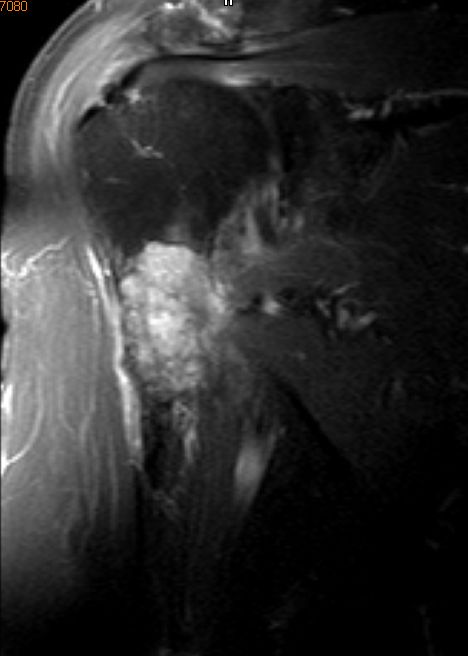

Humerus |

![]() |

![]() | ||||||||||||||||||